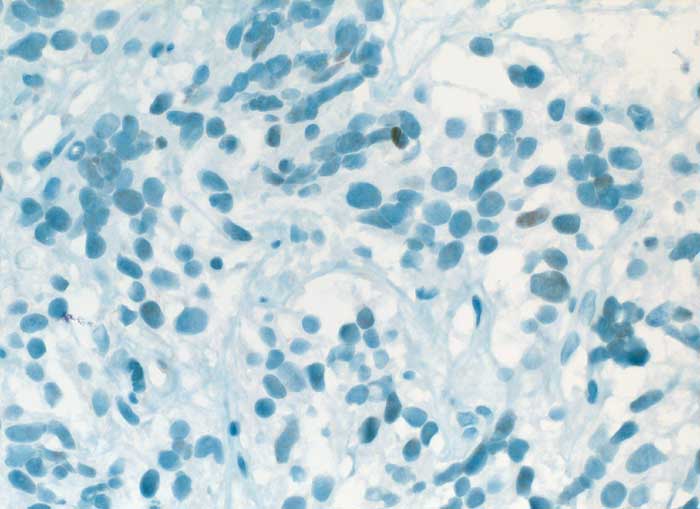

TTF-1

Anfärbung:

Zellkern

Reaktion im Normalgewebe:

TTF-1 wird exprimiert in follikulären Zellen der Schilddrüse, Typ II Pneumozyten, bronchiolären Zellen, Hypophysenvorderlappen, Nebenschilddrüse, C-Zellen und einigen Hirnregionen.